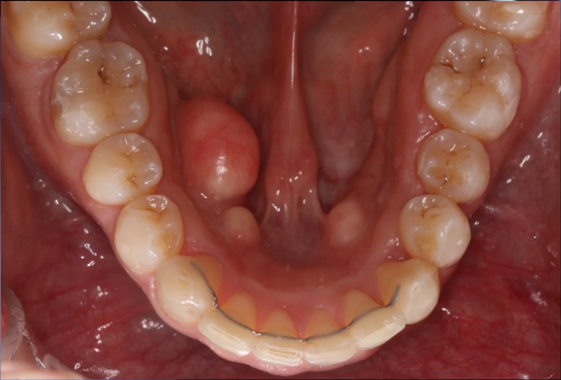

Four adult patients, seen by four different clinicians presented for orthodontic treatment with new orthodontic diagnostic terms of maxillary and mandibular hypoplasia with localized Orthodontosis and Orthodontitis (Figures 4–7),30 were successfully treated with the patented systems of FASTBRACES® Technologies. It is important to note that the universal orthodontic goal and accompanying treatment should be to successfully treat the biologically based diagnosis of the alveolar bone clinical morphology within a patient’s natural stable occlusion and morphologic appearance. Figure 4 holds particular significance as it sheds light on the complex nature of periodontal conditions, which involve multiple critical parameters. Notably, it reinforces the existing literature by demonstrating that the microbial flora surrounding tooth #25 or in an area already compromised by alveolar hypoplasia can progressively and rapidly deteriorate the alveolar bone.

Figure 4A Before Maxillary and Mandibular Orthodontosis and Orthodontitis of anterior teeth with localized severe gingival recession. The recession of #24 may be due to hypoplasia of #23 and #25 due to the fact that alveolar bone was not enough to sustain soft tissue coverage of #24.

Figure 4B Brackets are placed on lingually inclined mandibular teeth to facilitate alveolar bone restoration which in turns promotes the creation healthy soft tissue and the elimination of the hypoplasia (Orthodontosis). Note that brackets are not placed on labially positioned mandibular teeth.

Figure 4C Bracket placement on all teeth as previously lingually inclined roots are orthoerupted (man-made eruption).

Figure 4DAfter resolution of Maxillary and Mandibular Orthodontosis and Orthodontitis with restored alveolar bone and gingival architecture.